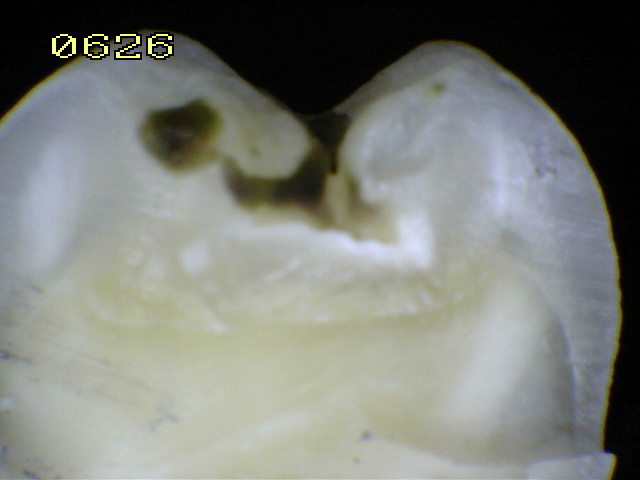

Espécimen Nº 28 |

| Corte sagital A:

Observe como el corte en la fosa presenta caries en dentina,

compatible con un código 2 histológico |

Corte sagital B: En la fisura es un

código 2 histológico |